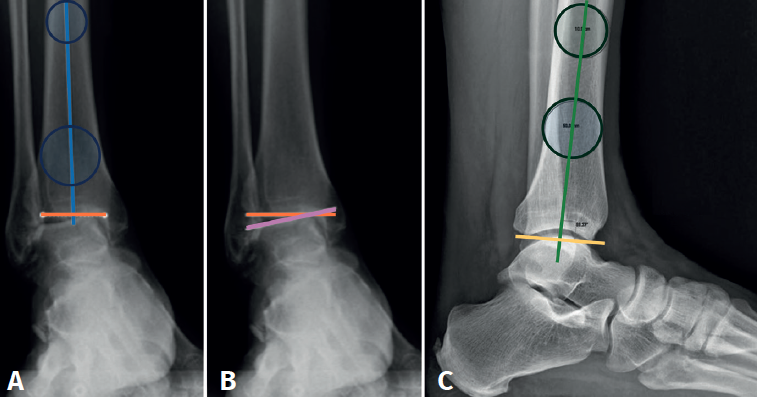

La alineación supramaleolar del tobillo debe evaluarse en los planos coronal y sagital, midiendo el ángulo tibial distal anterior y el ángulo tibial distal lateral, respectivamente.

En la proyección anterior de tobillo evaluaremos el talar tilt o ángulo de inclinación del astrágalo, aumentado en las lesiones incongruentes intraarticulares (Figura 1).

reaca.32284.fs2505013-figura1.png

Figura 1. A: ángulo tibial distal anterior, entre el eje anatómico de la tibia en el plano posteroanterior y la línea de la superficie articular distal de la tibia; B: ángulo de inclinación astragalina (talar tilt), formado entre la línea de la superficie articular tibial y la línea de la superficie articular astragalina. Evalúa la congruencia articular; C: ángulo tibial distal lateral, entre el eje anatómico lateral de la tibia y la línea de la superficie articular distal lateral de la tibia.

Debemos observar si, en las proyecciones laterales, existe una traslación anterior del astrágalo que muchas veces ocurre en estos fenómenos degenerativos crónicos asociados a inestabilidades (Figura 2).

Figura 2. Traslación anterior del astrágalo, característica de las artropatías tibioastragalinas secundarias a inestabilidades crónicas.